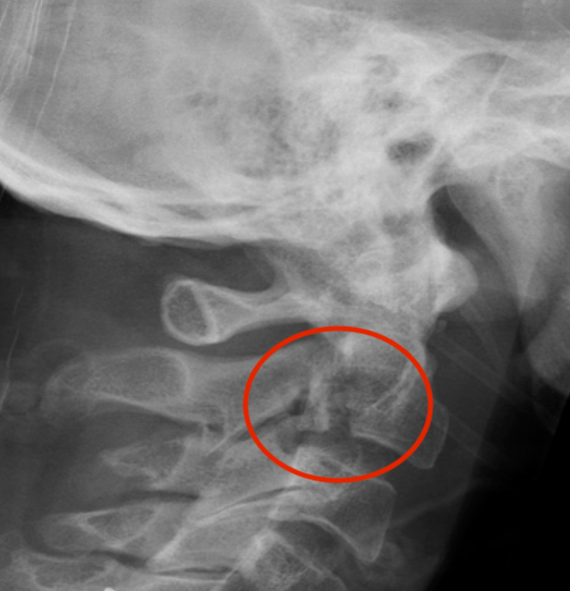

Hangman's fracture reduced and held in halo-vest

Post halo flexion and extension views demonstrating fracture stability